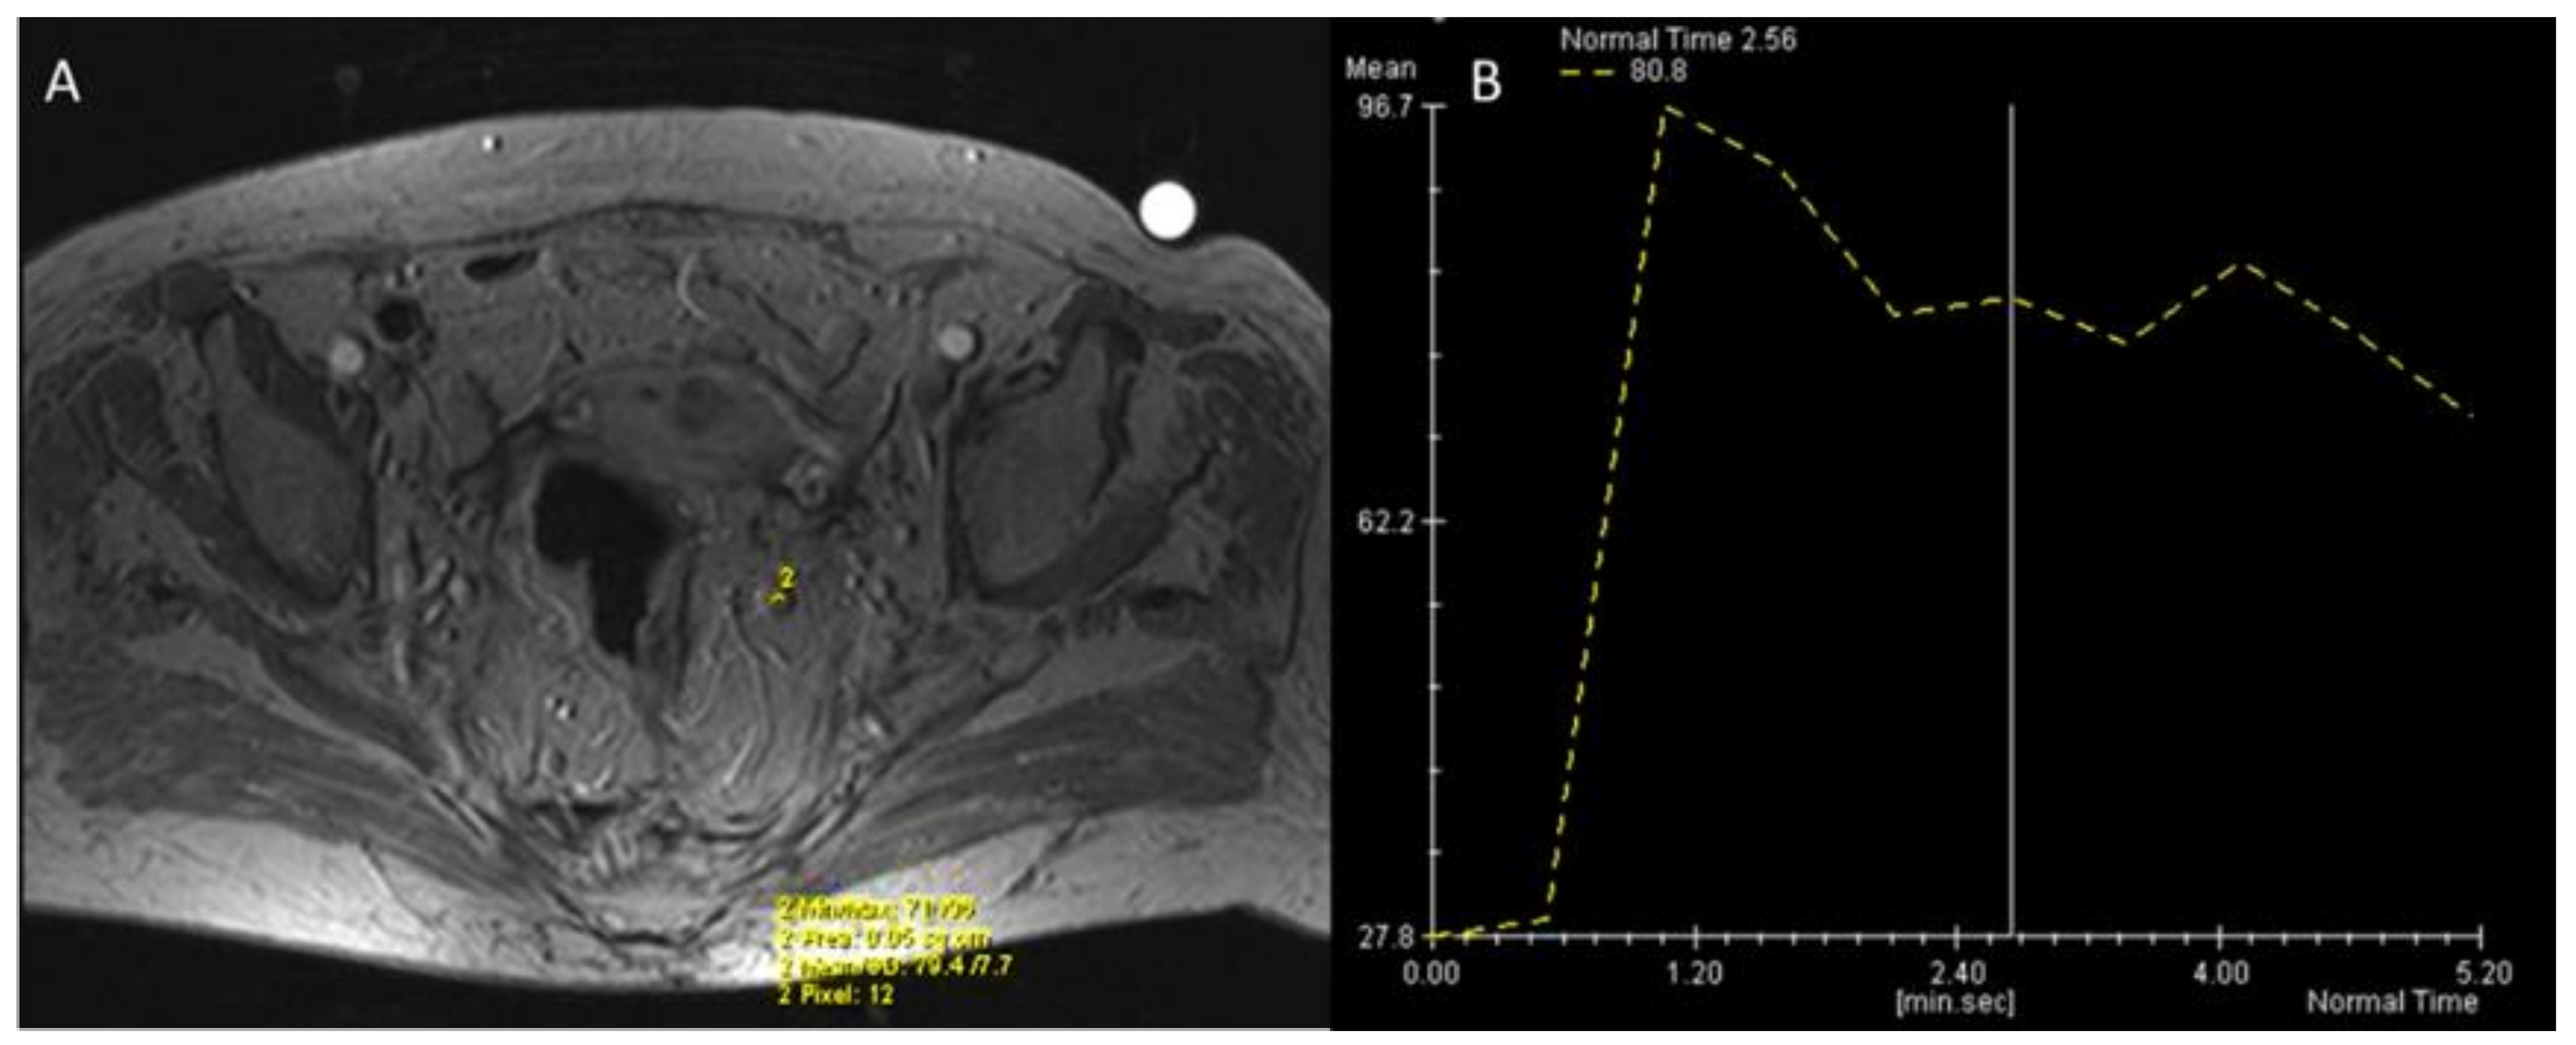

- Petrillo, A.; Fusco, R.; Petrillo, M.; Granata, V.; Bianco, F.; Marzo, M.D.; Delrio, P.; Tatangelo, F.; Botti, G.; Pecori, B.; et al. DCE-MRI Time–Intensity Curve Visual Inspection to Assess Pathological Response after Neoadjuvant Therapy in Locally Advanced Rectal Cancer. Jpn. J. Radiol. 2018, 36, 611–621. [Google Scholar] [CrossRef] [PubMed]

- Alberda, W.J.; Dassen, H.P.N.; Dwarkasing, R.S.; Willemssen, F.E.J.A.; van der Pool, A.E.M.; de Wilt, J.H.W.; Burger, J.W.A.; Verhoef, C. Prediction of Tumor Stage and Lymph Node Involvement with Dynamic Contrast-Enhanced MRI after Chemoradiotherapy for Locally Advanced Rectal Cancer. Int. J. Color. Dis. 2012, 28, 573–580. [Google Scholar] [CrossRef]

- Petrillo, A.; Fusco, R.; Petrillo, M.; Granata, V.; Sansone, M.; Avallone, A.; Delrio, P.; Pecori, B.; Tatangelo, F.; Ciliberto, G. Standardized Index of Shape (SIS): A Quantitative DCE-MRI Parameter to Discriminate Responders by Non-Responders after Neoadjuvant Therapy in LARC. Eur. Radiol. 2015, 25, 1935–1945. [Google Scholar] [CrossRef] [PubMed] [Green Version]

- Fusco, R.; Petrillo, A.; Petrillo, M.; Sansone, M. Use of Tracer Kinetic Models for Selection of Semi-Quantitative Features for DCE-MRI Data Classification. Appl. Magn. Reson. 2013, 44, 1311–1324. [Google Scholar] [CrossRef]

- Fusco, R.; Granata, V.; Sansone, M.; Rega, D.; Delrio, P.; Tatangelo, F.; Romano, C.; Avallone, A.; Pupo, D.; Giordano, M.; et al. Validation of the Standardized Index of Shape Tool to Analyze DCE-MRI Data in the Assessment of Neo-Adjuvant Therapy in Locally Advanced Rectal Cancer. Radiol. Med. 2021, 126, 1044–1054. [Google Scholar] [CrossRef]